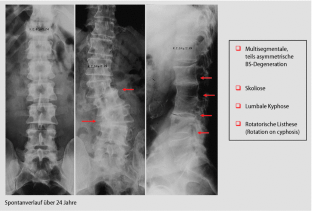

Abb. 4